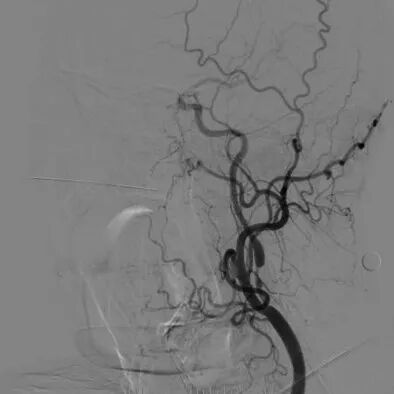

心脑联合造影

-- 右侧颈内起始部中度狭窄,经前交通向左侧代偿

-- 左侧颈内起始部重度狭窄

波科支架怎么样​径技·第165期|7F经桡入路下的颈动脉狭窄支架成形术一例_https://www.jmylbn.com_新闻资讯_第14张

波科支架怎么样​径技·第165期|7F经桡入路下的颈动脉狭窄支架成形术一例_https://www.jmylbn.com_新闻资讯_第15张

波科支架怎么样​径技·第165期|7F经桡入路下的颈动脉狭窄支架成形术一例_https://www.jmylbn.com_新闻资讯_第16张

波科支架怎么样​径技·第165期|7F经桡入路下的颈动脉狭窄支架成形术一例_https://www.jmylbn.com_新闻资讯_第17张

-- 右侧椎动脉起始部中度狭窄

-- 左侧椎基底动脉无明显异常